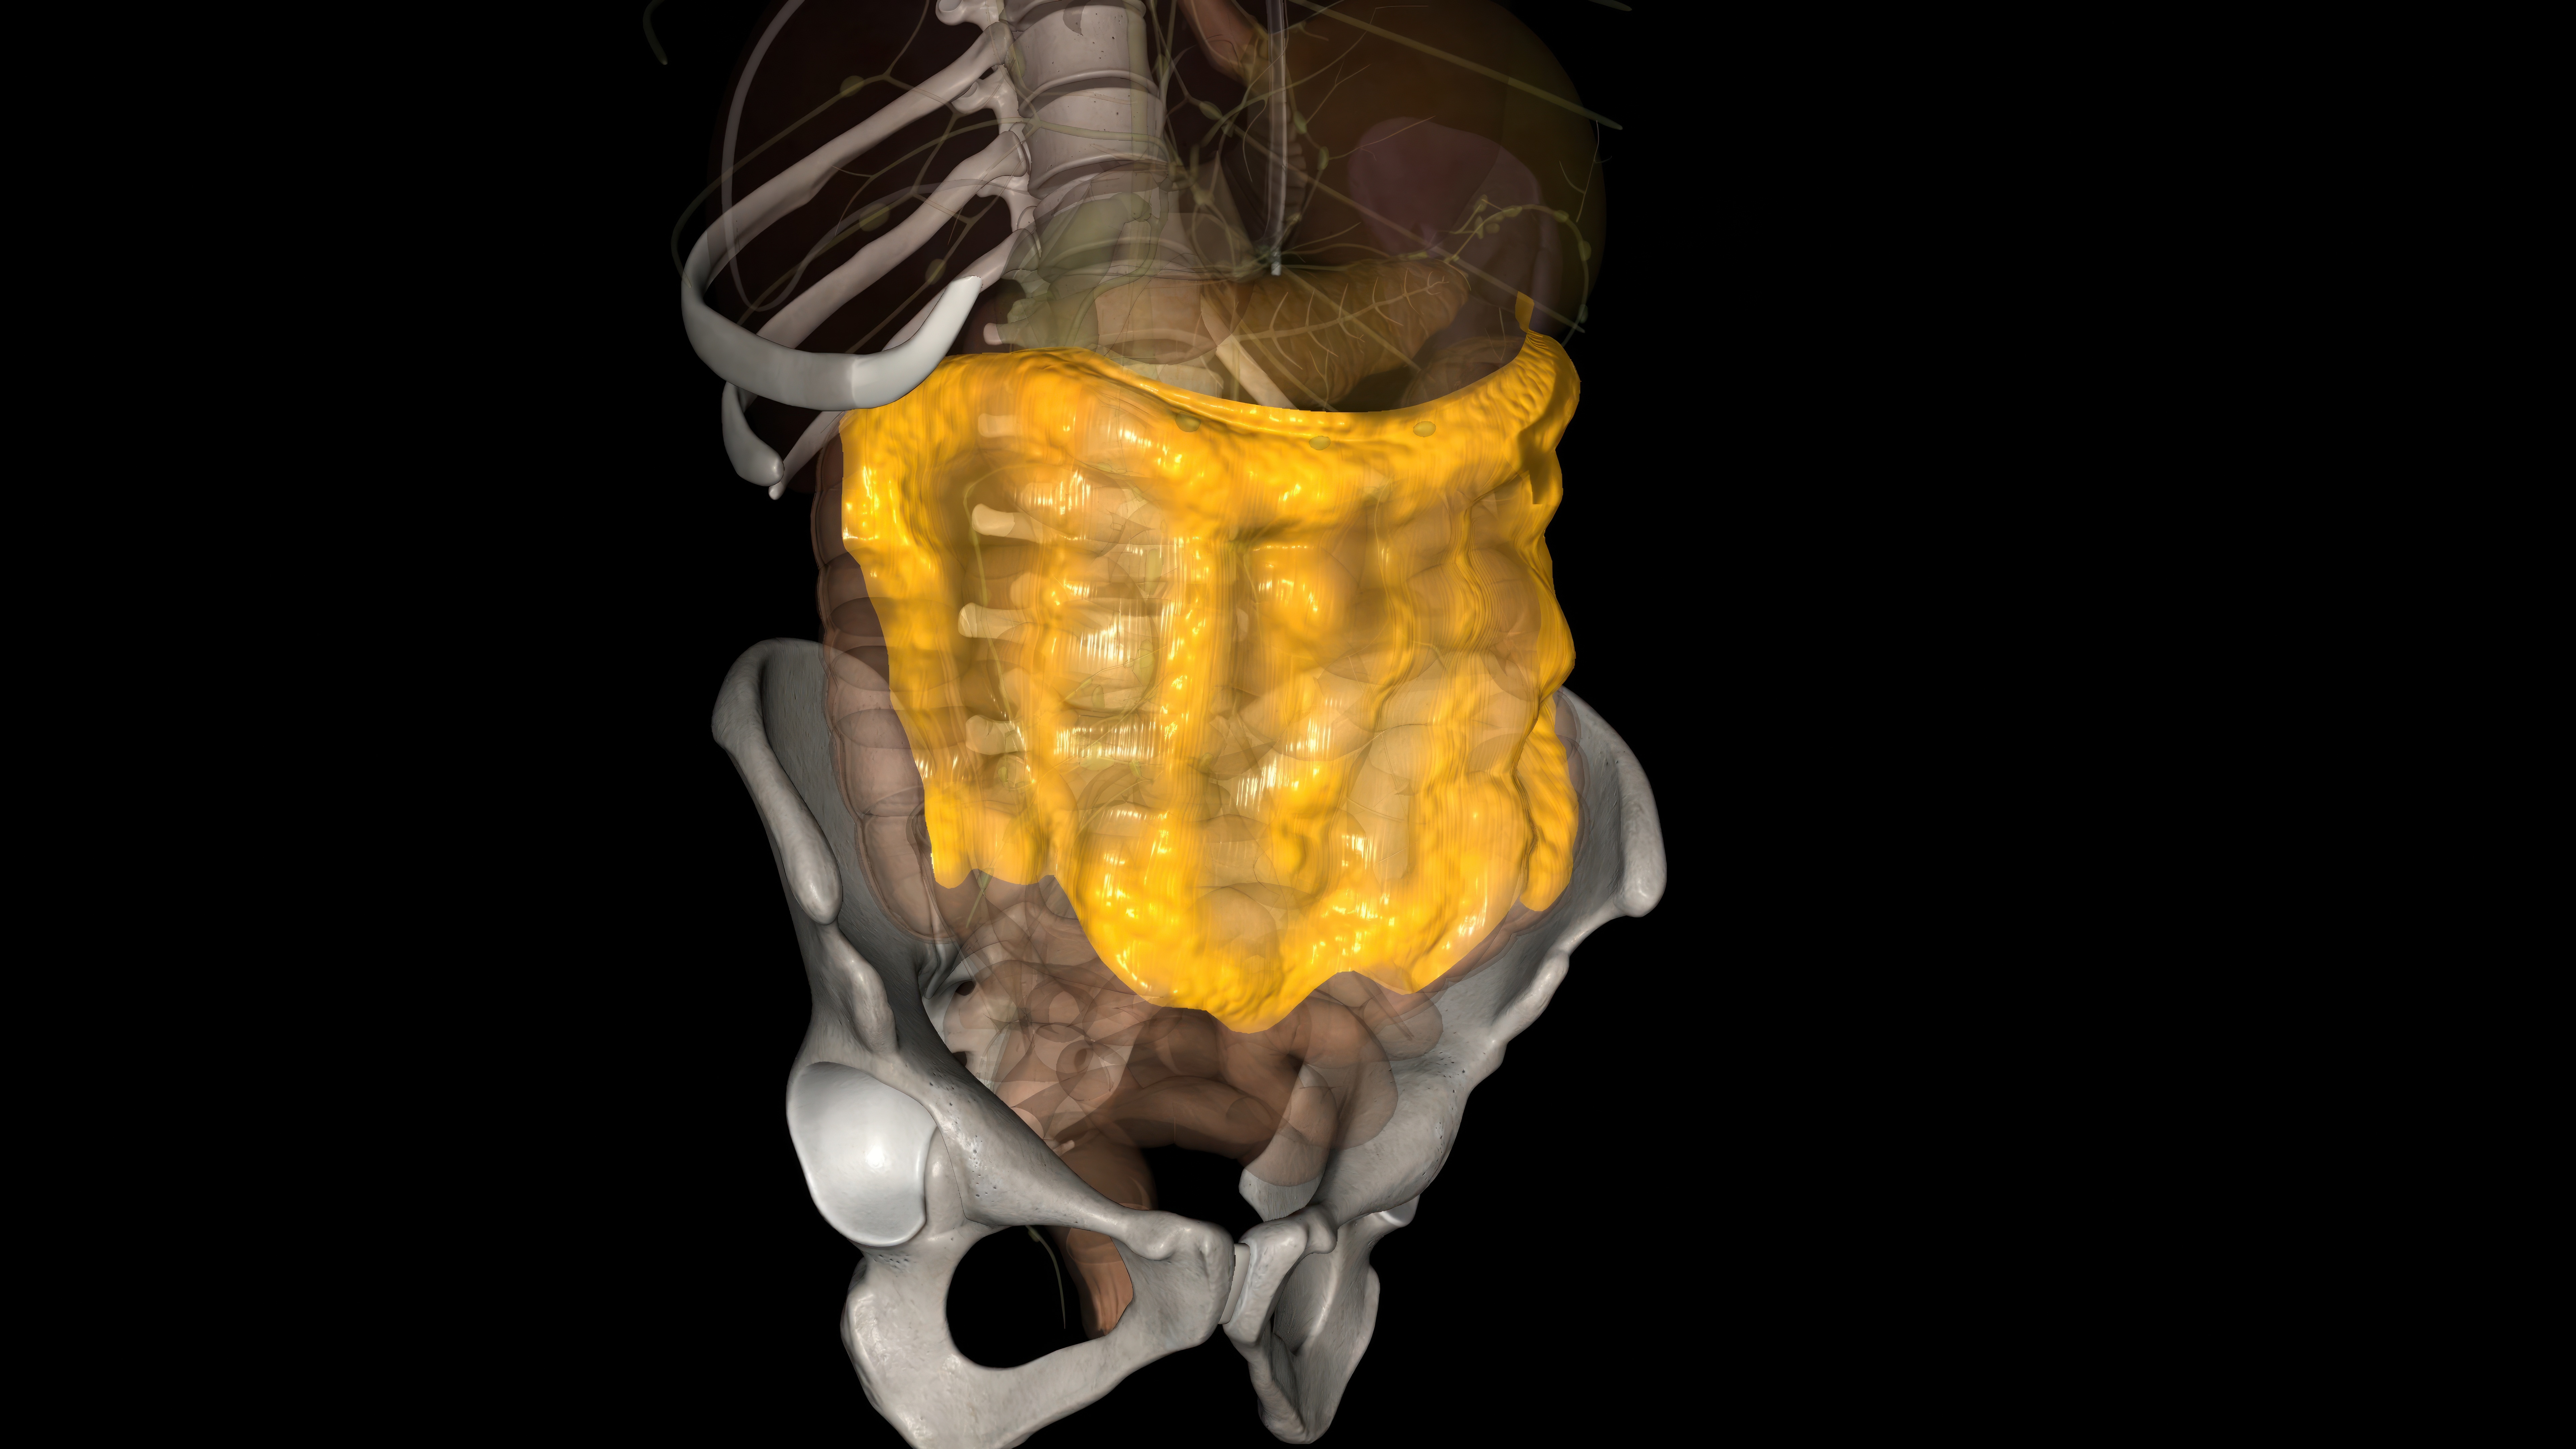

8.“We don’t fully understand the omentum’s function. For years it was thought to be just connective tissue in the gut, but now we’ve learned it’s a whole organ affecting the gut-brain axis that we have very little understanding of.”

9.“The gut microbiome. While it’s well-known that the gut plays a huge role in digestion, researchers are discovering just how much our gut bacteria affect other parts of our health, like mood, immunity, and even brain function.”